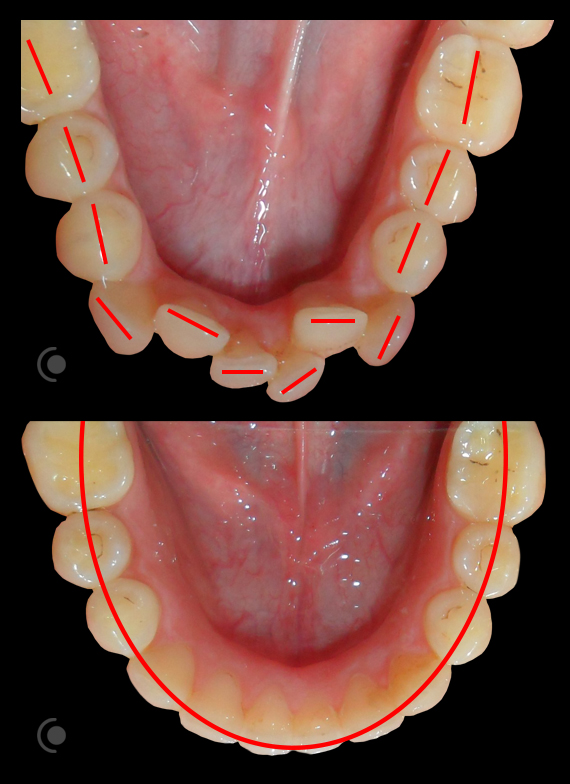

O našoj kvaliteti najbolje govore naši rezultati!

Centar za ortodonciju Petra Džapo